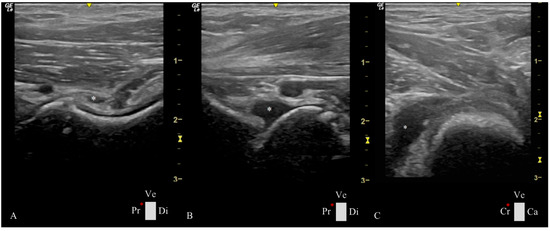

2.3. Ultrasonographic Ventral Hip Joint Approach

- -

- Longitudinal Femoral Head–Neck Plane

- Transverse Femoral Head–Neck Plane